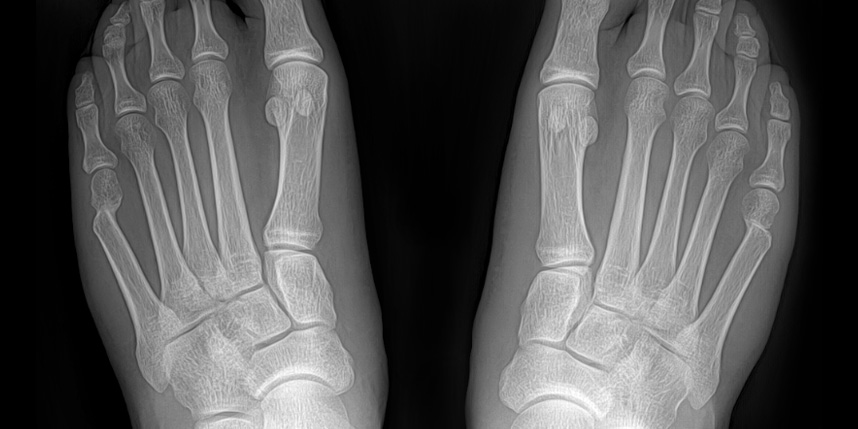

소건막류는 새끼발가락 관절의 뿌리 부분이 바깥쪽으로 튀어나오면서 발생하는 변형입니다.

이 튀어나온 부분이 신발과 마찰을 일으켜 통증, 염증, 굳은살 등을 유발할 수 있습니다.

엄지발가락이 휘면서 돌출되는 무지외반증처럼 새끼발가락쪽에 외반 변형이 생긴 것을 의미합니다.